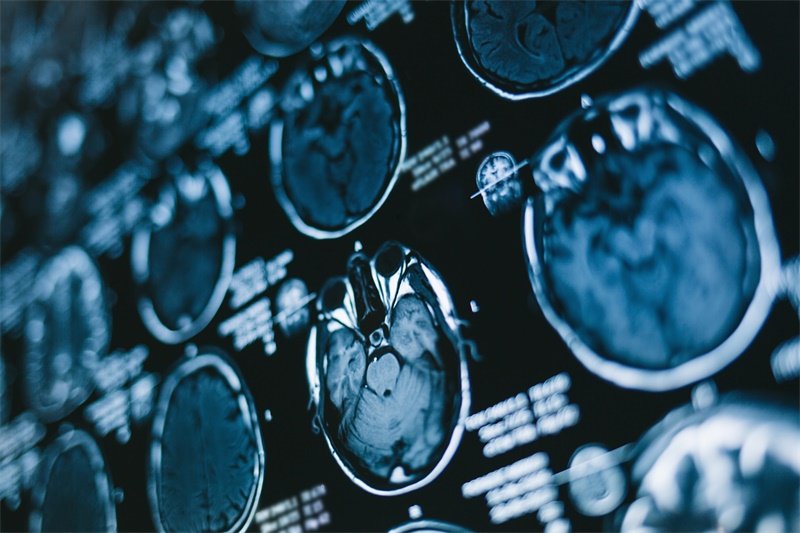

磁共振成像(MRI)的重要性

磁共振成像(MRI)是评估鞍区占位的金标准,能够提供清晰的组织图像,帮助医生识别病变的性质与大小。

在MRI影像中,正常的鞍区表现为均匀的信号,周围结构边界清晰。而如果存在鞍区占位,影像上则表现为相对不均匀或局部肿块,信号特征因病变性质而异。

CT扫查的局限性

虽然计算机断层扫描(CT)在一些情况下也可以用于鞍区占位的评估,但它的分辨率通常低于MRI,因此通常不作为首选。CT主要用于评估骨骼结构是否受到损伤,或在无法进行MRI的情况下应用。